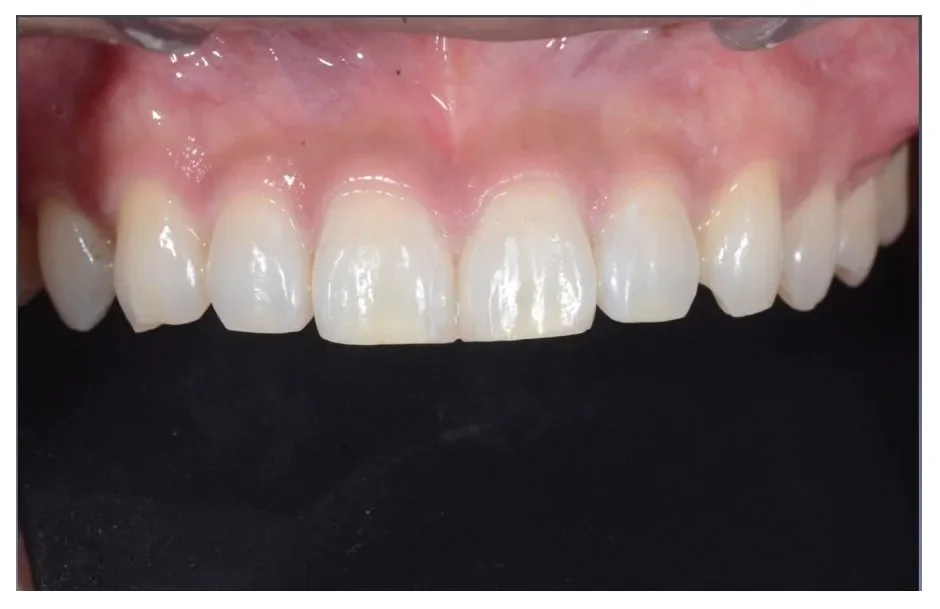

Before

After

ダイレクトボンディングの症例2

2週間、3回 / 88,000円リスク・副作用:経年的に歯間が開いてくる可能性及び接着低下によりレジン脱離、レジン周囲変色